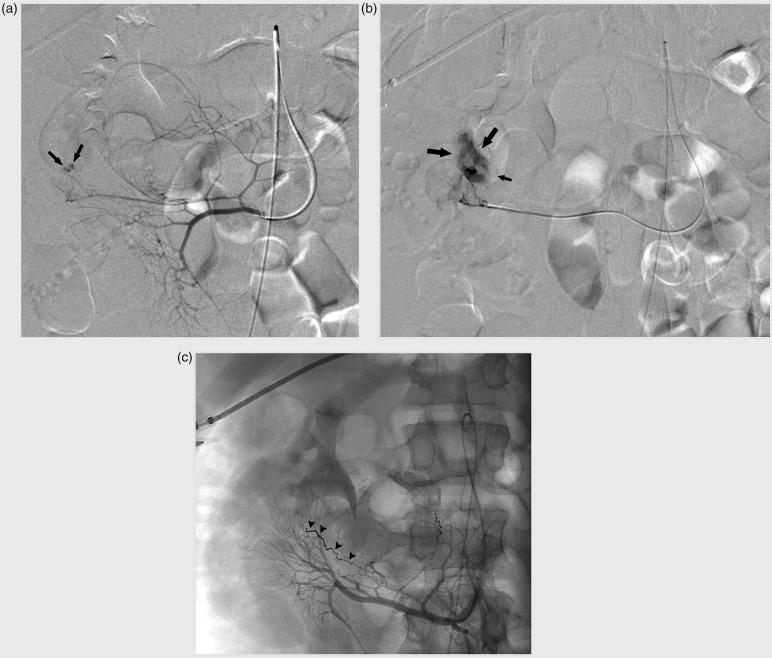

A 23-year-old man presented with hypovolemic shock due to a lower gastrointestinal bleeding. Radiological and endoscopic investigation did not reveal the bleeding site. Emergency visceral angiography showed contrast extravasation at a right-sided branch of the superior mesenteric artery (SMA). Embolization of the bleeding point was performed, resulting in bleeding cessation. One week later, the patient presented with a new episode of moderate anal blood loss associated with diffuse abdominal pain. Computed tomography (CT) revealed an ischemic small bowel diverticulum that was treated by a laparoscopically-assisted segmental small bowel resection. Intraoperative and pathologic analysis confirmed a post-embolization ischemic diverticulitis of Meckel.